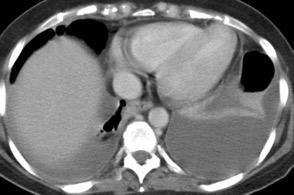

Naidich DP et al. Computed tomography of the diaphragm: peridiaphragmatic fluid localization.J Comput Assist Tomogr1983.

En el corte axial, el líquido pleural se sitúa por detrás